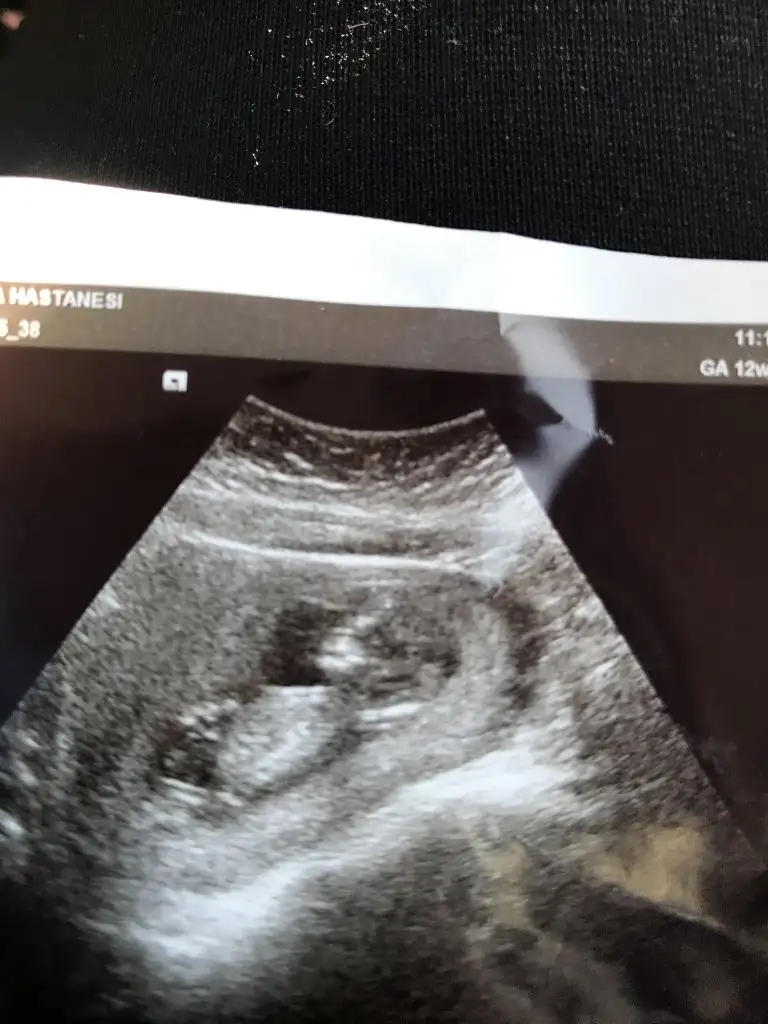

Net değil usg erkek olabilirEki Görüntüle 2728955 Banada bakar musun cnm12+4

Tam net belli değil usgde bebegin alt kısmı kordon değilse nub teorisine göre erkek olabilir bence tahmin ettimPeki nerden anladınız erkek olabileceğini genelde Kıza benzettilerde o yüzden soruyorum

Tam net belli değil usgde bebegin alt kısmı kordon değilse nub teorisine göre erkek olabilir bence tahmin ettim